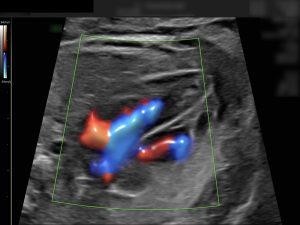

Mit der Feindiagnostik lassen sich alle sichtbaren Organe prüfen, das Herz und die Durchblutung in den Gebärmutterarterien kontrollieren. Ein Ultraschall kann jedoch nie alle körperlichen oder chromosomalen Auffälligkeiten ausschließen.